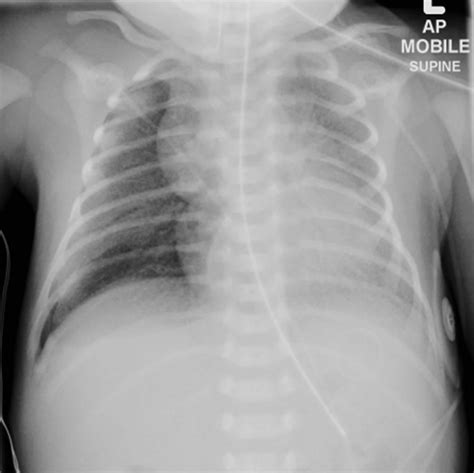

ARDS is a complex syndrome that can be triggered by various factors, including sepsis, pneumonia, trauma, and aspiration. It is marked by the rapid onset of bilateral pulmonary infiltrates, refractory hypoxemia, and decreased lung compliance. The Ards Chest X Ray is instrumental in visualizing these pulmonary infiltrates, which appear as diffuse, bilateral opacities on the radiograph.

The Ards Chest X Ray is often the first imaging modality used to evaluate patients suspected of having ARDS. It provides a quick and relatively inexpensive way to assess the lungs for signs of inflammation and edema. Key findings on an Ards Chest X Ray include:

• Bilateral pulmonary infiltrates

• Diffuse opacities

• Air bronchograms (air-filled bronchi surrounded by consolidated lung tissue)

• Absence of pleural effusions or cardiomegaly

These findings, when combined with clinical criteria such as the PaO2/FiO2 ratio (the ratio of arterial oxygen partial pressure to fractional inspired oxygen), help confirm the diagnosis of ARDS.

• Bilateral Infiltrates: ARDS typically presents with bilateral, diffuse infiltrates that are often more pronounced in the dependent lung zones.

• Air Bronchograms: These are visible air-filled bronchi within consolidated lung tissue and are a hallmark of ARDS.

• Absence of Pleural Effusions: Unlike other causes of pulmonary edema, ARDS is usually not associated with significant pleural effusions.

• Cardiomegaly: The heart size is typically normal in ARDS, helping to differentiate it from cardiogenic pulmonary edema.